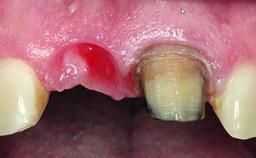

A 15-year-old male patient was referred to us by his pediatric dentist in June 2004 for evaluation of treatment options for his failing tooth 21. The patient had recently seen an endodontist for internal bleaching and been advised that there had been significant resorption and ankylosis. The patient’s mother was concerned because the tooth appeared shorter than the adjacent one. His past dental history was significant for trauma (September 2001), where the tooth had been avulsed and reimplanted. Teeth 11 and 21 had been endodontically treated.